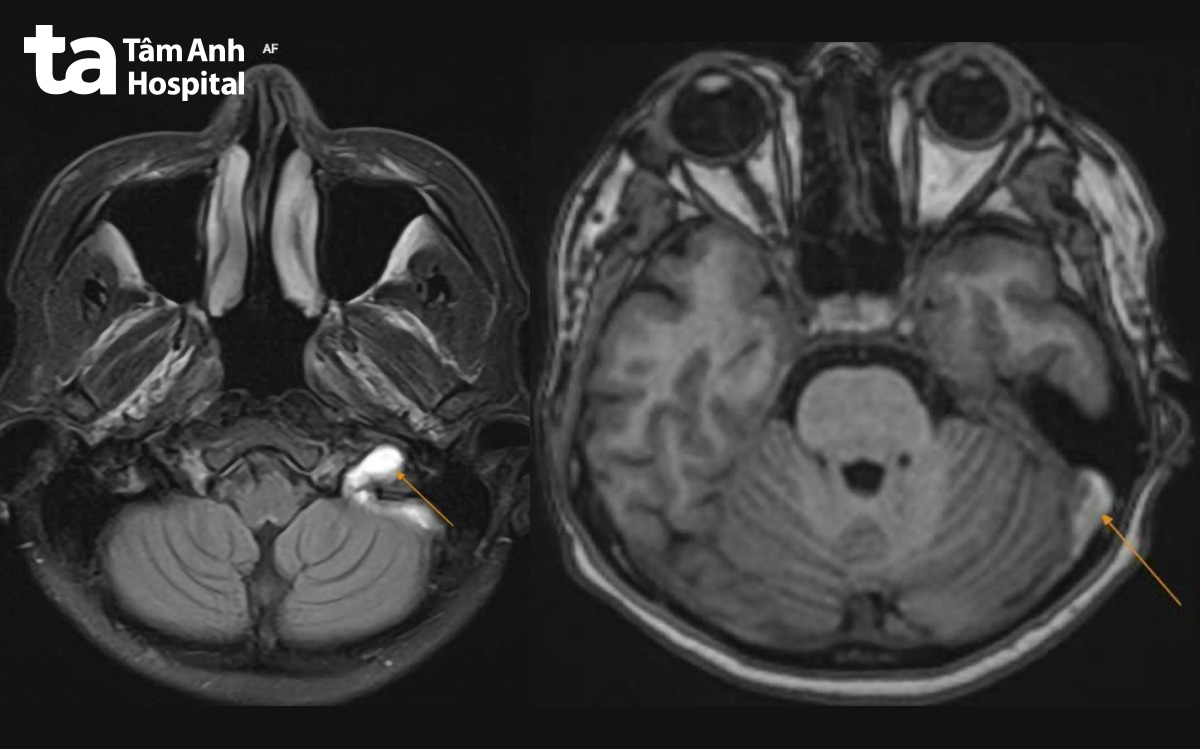

Kết quả cho thấy có cục máu khối hình thành ở tĩnh mạch cảnh trong bên trái, gần như làm tắc nghẽn dòng máu tại đoạn hành. Huyết khối đang ở giai đoạn bán cấp và đã lan lên xoang sigma, một phần xoang ngang bên trái. yKhai thác tiền sử, chị Mai cho biết đã sử dụng thuốc tránh thai hằng ngày trong khoảng một năm.